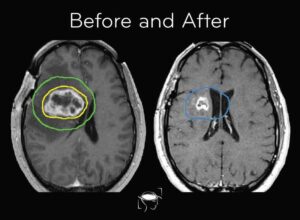

- MRI scans every 2–3 months

Through MRI imaging and confirmed by surgical biopsy, followed by histopathology and molecular testing.